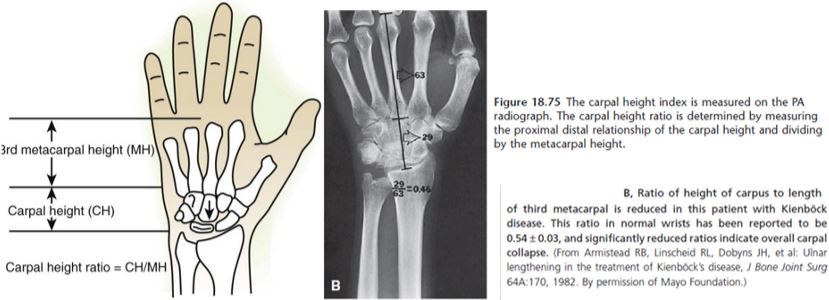

Como é realizado o método de Youm para avaliar altura carpal

A

Base do 3° meta até art do rádio

___________________________

comp do 3° meta

Qual o valor normal da altura carpal pelo metodo de youm

0,54 + ou - 0,03